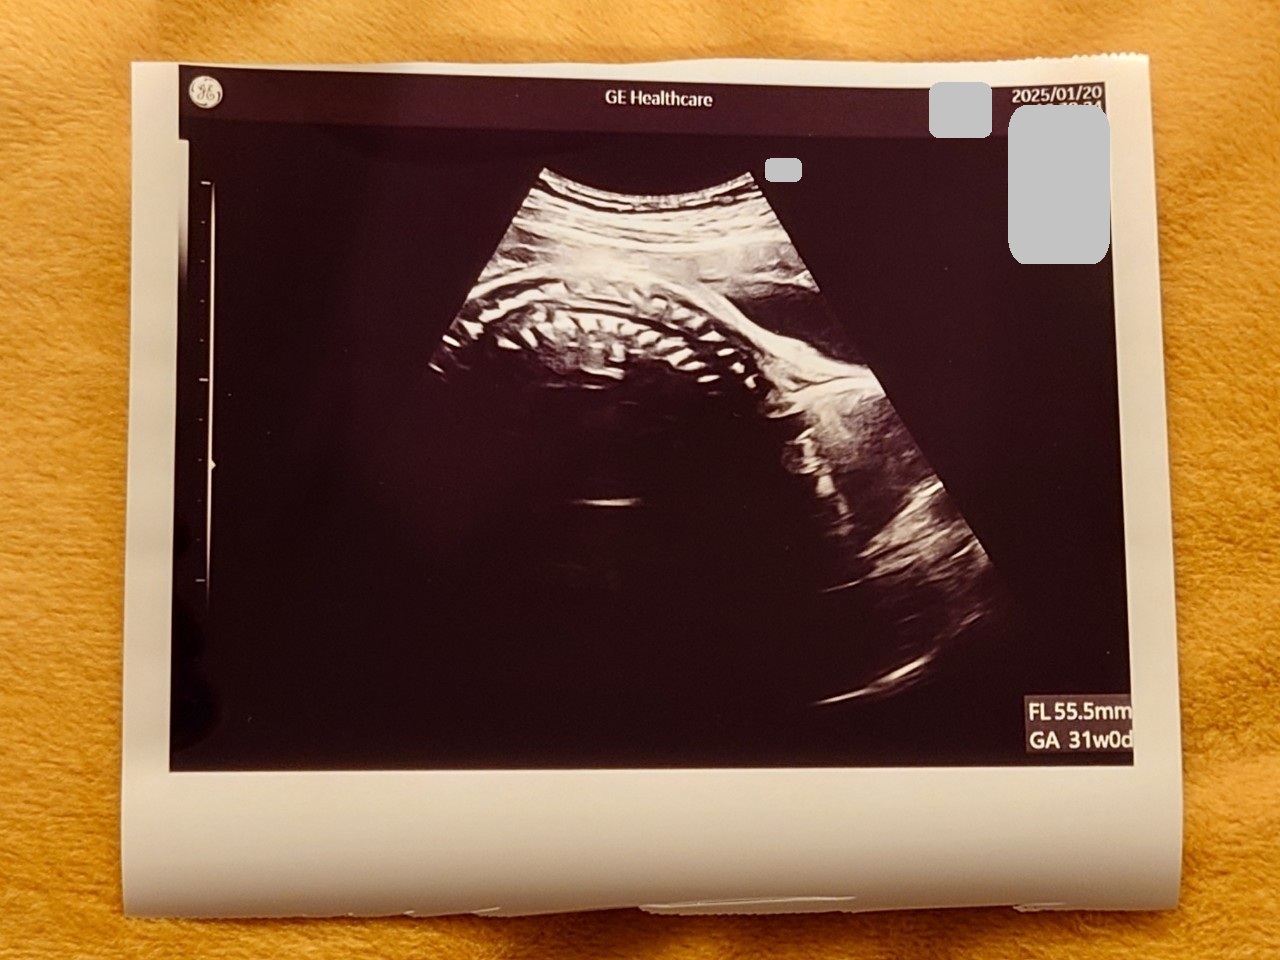

妊娠28週2日目:定期健診の日

2週間に1回のペースに変わった健診!

この日はベビちゃんの位置が悪くて全然エコーで見えない👶🤣

上の画像も背骨?を映したものかな~って感じ💨